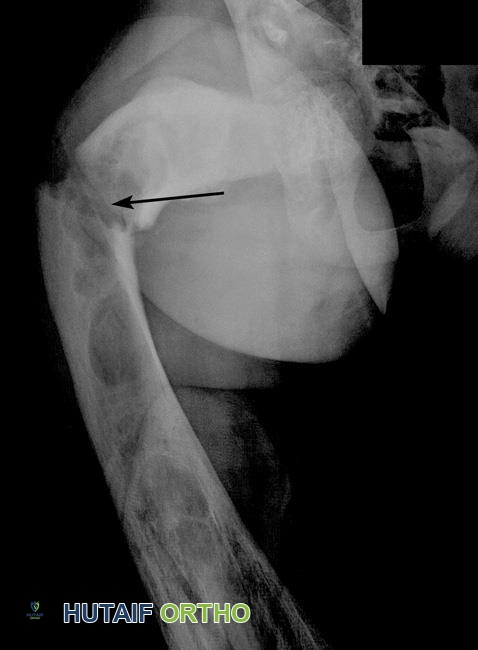

يُظهر هذا الفحص بالأشعة السينية كسرًا في عظم الفخذ نتيجة لخلل التنسج الليفي، مشار إليه برأس السهم.

تُظهر هذه الأشعة السينية استخدام غرسات معدنية لتثبيت عظم فخذ قد كُسر بسبب خلل التنسج الليفي.